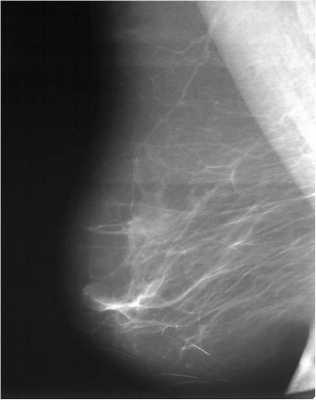

Для выявления злокачественных опухолей молочной железы существует определенный алгоритм диагностики, и его первичный элемент — маммографический скрининг. Чувствительность этого метода диагностики для опухолей от 2 мм до 5 мм составляет около 85%. Маммографическое исследование выполняют в двух проекциях.

УЗИ молочной железы способно визуализировать узловое образование, но связь его с протоком не всегда очевидна, тем не менее, при плотном строении молочной железы разрешающая способность сонографии выше маммографического исследования.

При стандартной маммографии карцинома в протоке не всегда обнаруживается, зачастую о её существовании догадываются по расширению протока и его деформации. О злокачественной природе свидетельствует скопление глыбок кальция в извитых сосудах опухоли, но обызвествление присутствует не всегда.